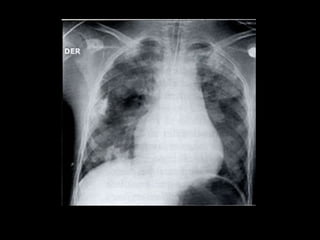

Hemorragia pulmonar na síndrome de

Goodpasture.

HEMORRAGIA PULMONAR  Podeocorrer por : traumatismos, diátese hemorrágica, aspergilose invasiva, pseudomonas, gripe, drogas, embolia, SDRA, doenças auto-imunes .  As radiografias mostram opacidades bilaterais indistinguíveis do edema pulmonar.  Resolução completa ocorre em 2 semanas.  Prognóstico sombrio.

Hemorragia pulmonar nasíndrome de Goodpasture.